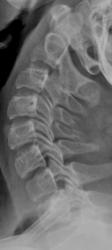

Интересное наблюдение. Думаю синостоза тут нет, есть подвижность в этом сегменте, прослеживаются суставные щели в дугооотросчатых суставах это хорошо видно на функц.снимках

Раньше попадался на эту удочку, просто суставы не в плоскости хода лучей, именно в этом сегменте чаще создаются такие условия съемки. Иллюстрация весьма кстати к вопросу о взаимосмещаемости п-ков в сагиттальной плоскости.